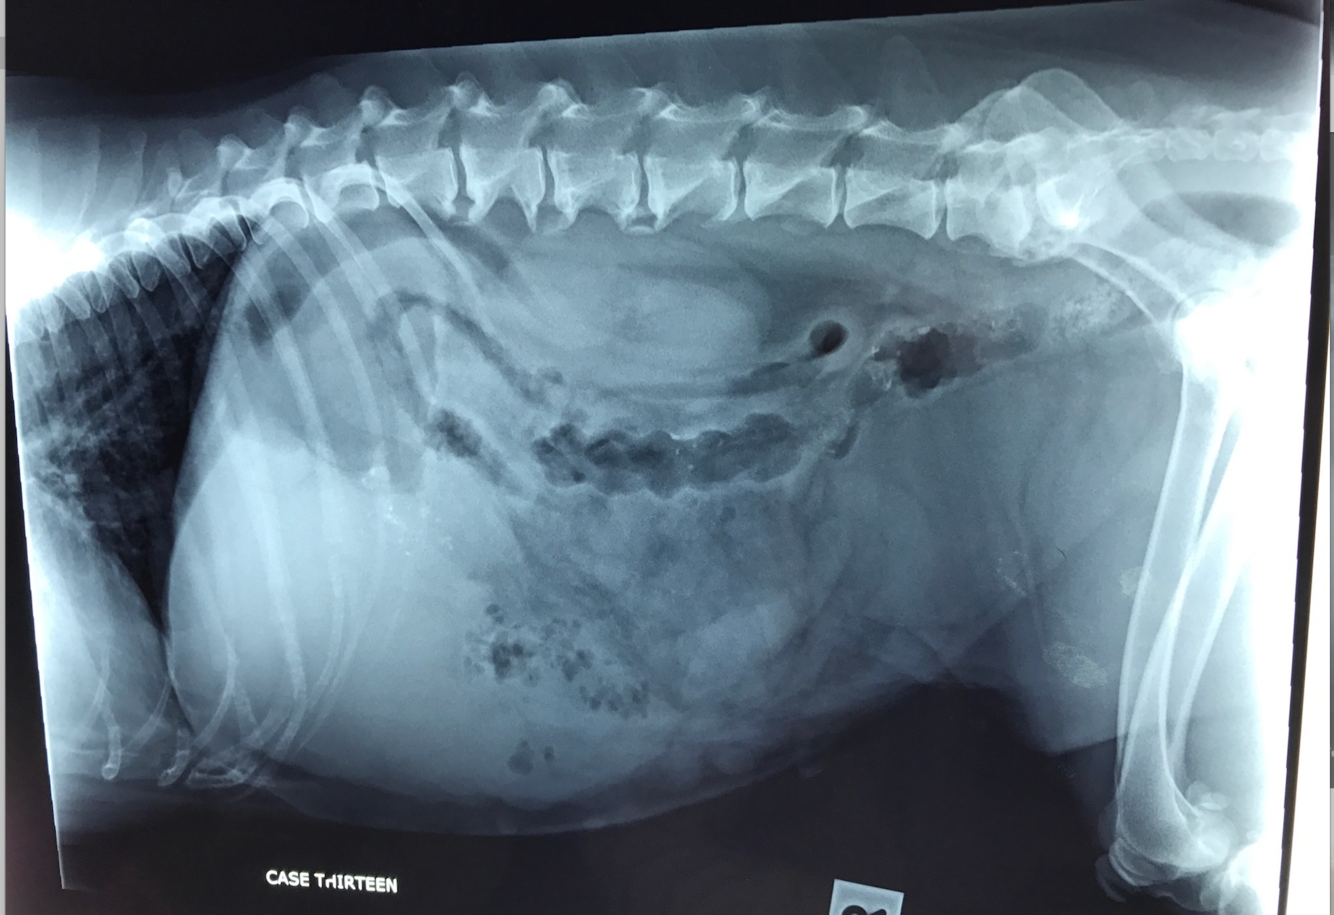

12 yo MN Labradoodle

Acute v+, lethargy, and profound weakness, but concurrent history of chronic vomiting and weight loss

HR 160 with injected MM

panting

Relaxed abdomen– firm area cranio ventrally– mass?? Cannot rule out tail of spleen

Gas filled stomach– rule for distension?

Over distended SI– what is the rule to assess for presence of mechanical SI obstruction?

The over distended SI loop within the mid ventral abdomen containing multiple fragmented gas opacities… what do you think this is most likely to be?

Ventral spondylosis L2-3

What is your plan for Austen